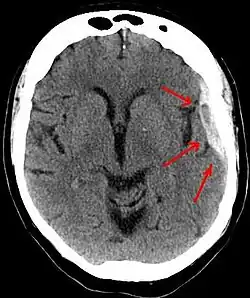

Os hematomas subdurais ocorrem mais freqüentemente no topo e partes laterais frontais e lobos parietais.[2][11] Também são frequentes na fossa posterior do crânio, e perto da foice cerebral e do tentório.[2] Ao contrário hematomas epidurais , que não podem expandir-se através das suturas do crânio, os hematomas subdurais podem expandir-se no interior do crânio, criando uma forma côncava que se segue a curva do cérebro, bloqueados apenas pelas reflexões durais como o tentório e a foice cerebral. Em uma tomografia computadorizada, os hematomas subdurais são classicamente em forma de crescente, com uma superfície côncava distal ao crânio. No entanto, eles podem ter uma aparência convexa, especialmente na fase inicial do sangramento. Isso pode causar dificuldade em distinguir entre as hemorragias subdural e epidural. Um indicador mais fiável de hemorragia subdural é o envolvimento de uma parcela maior do hemisfério cerebral, já que pode cruzar as linhas de sutura, ao contrário de uma hemorragia epidural. Sangue subdural também pode ser visto como uma densidade de camadas ao longo da membrana tentorial . Isto pode ser um processo crónico estável, uma vez que o sistema de alimentação é de baixa pressão. Em tais casos, os sinais sutis de hemorragia como o apagamento dos sulcos ou o deslocamento mediano da junção entre a matéria cinzenta e matéria branca podem ser aparentes. Um sangramento crônico pode ter a mesma densidade do tecido cerebral (chamado isodenso ao cérebro), o que significa que ele vai aparecer na TC como o mesmo tom que o tecido cerebral, potencialmente mascarando a lesão.